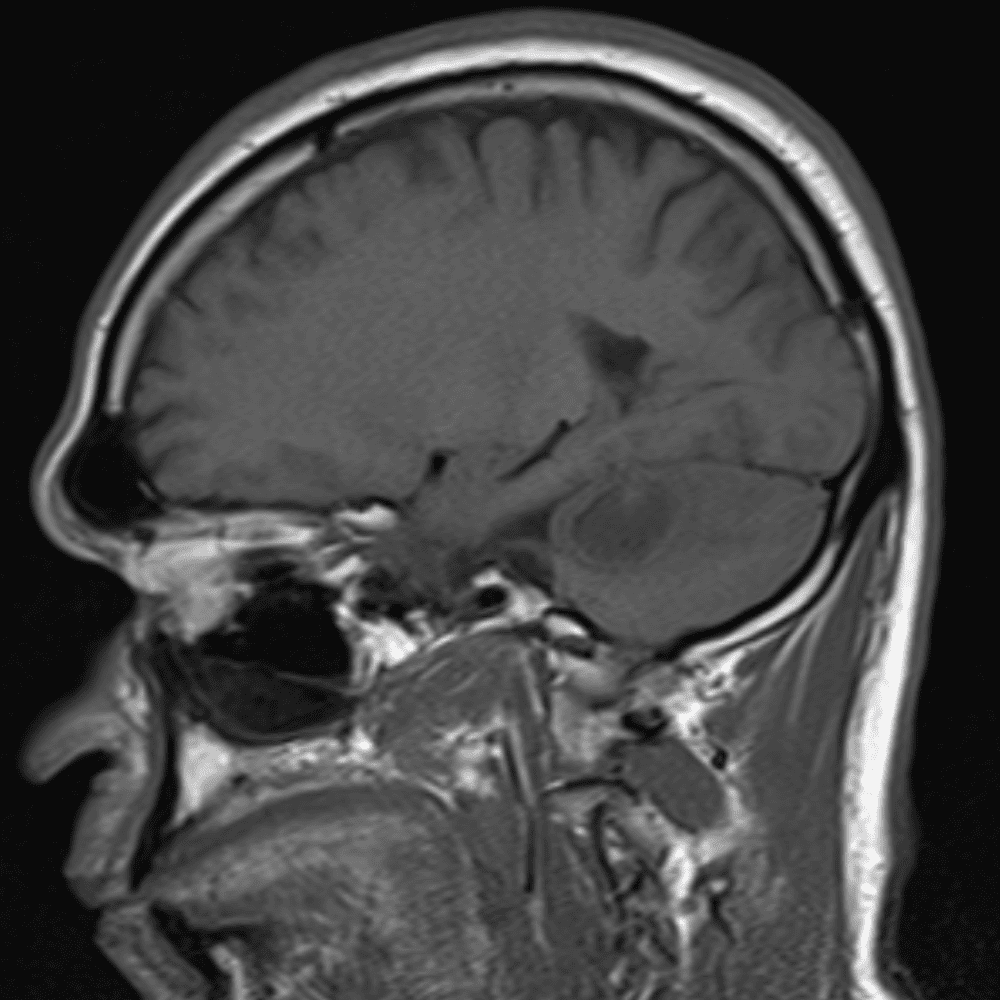

๋ฏธ๋ฌ˜ํ•˜๊ฑฐ๋‚˜ ์–ด๋ ค์šด ์‚ฌ๋ก€์™€ ์ผ๋ถ€ ์ •์ƒ ์‚ฌ๋ก€๋ฅผ ํฌํ•จํ•˜์—ฌ ๋‹น์ง์„ ์‹œ๋ฎฌ๋ ˆ์ด์…˜ํ•ฉ๋‹ˆ๋‹ค.

50 ์‚ฌ๋ก€